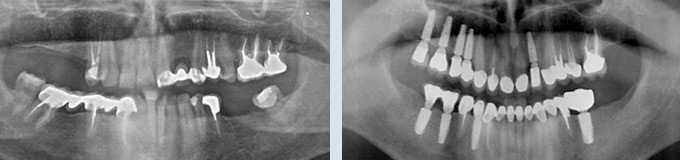

Il me manque de nombreuses dents, les autres sont perdues, je veux l’idéal.

Solution : on peut remplacer toutes vos racines manquantes ou perdues par autant de racines artificielles et vous redonner des dents fixes partout.

Toutes dents sont hélas perdues. Toutes les dents absentes sont remplacées par des couronnes sur implants.

J’ai des caries partout, des dents manquantes, je veux l’idéal.

Toutes les dents manquantes sont remplacées et le sourire refait.